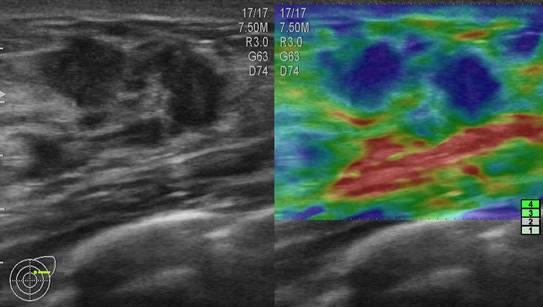

Ung thư vú

» Thông tin: Nữ giới – 25 tuổi.

» Lâm sàng: Khối tuyến vú.